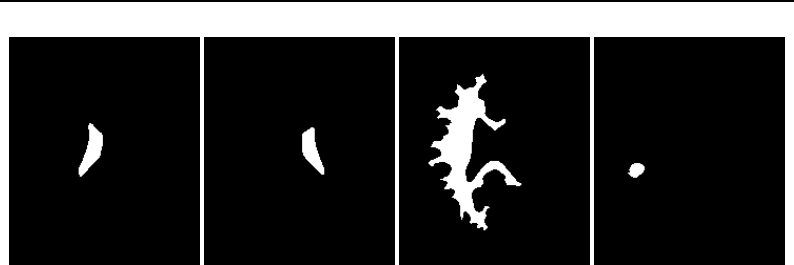

The National Library of Medicine Insight Segmentation and Registration Toolkit, shortened as the

Insight Toolkit (ITK), is an open-source software toolkit for performing registration and segmenta-

tion. Segmentation is the process of identifying and classifying data found in a digitally sampled

representation. Typically the sampled representation is an image acquired from such medical instru-

mentation as CT or MRI scanners. Registration is the task of aligning or developing correspondences

between data. For example, in the medical environment, a CT scan may be aligned with a MRI scan